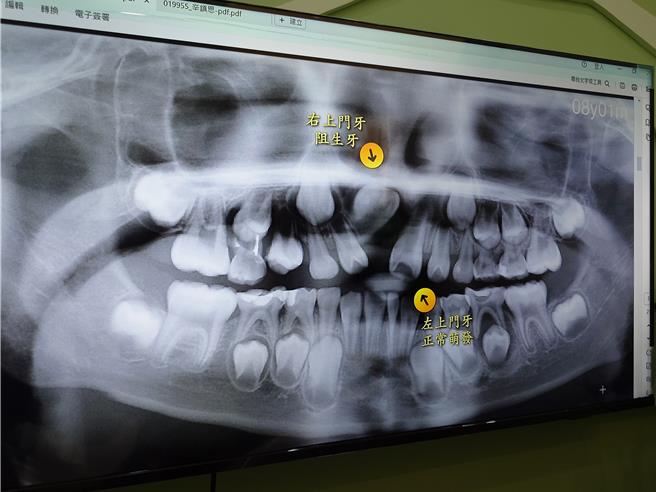

高雄2名小学生门牙大多已长齐,却独漏1颗迟迟未长出,一照X光发现竟长歪了,其中1名更向上生长,若放任不管恐从鼻孔冒出,牙医师表示其实是「阻生齿」作祟,透过手术搭配矫正治疗,即可恢復健全牙齿,同时建议家长多加留意孩童换牙期状况。

1名8岁的陈小弟,因曾经摔断过门牙,但周边牙齿已陆续换牙为成人牙齿,但断牙处却迟迟没长出来,导致讲话容易「漏风」让家长好担心,直到学校例行健康检查才发现,该处门牙竟是向上生长,让家长赶紧带到牙科进行治疗。

还有1名9岁的辛小弟,同样发现周遭门牙都已长齐,唯独1颗迟迟未出现,辛小弟妈妈想到,自己亲弟弟小时候也发生类似状况,直觉有「阻生齿」发生,因此带辛小弟到牙科就诊,发现辛小弟牙齿已向外突出不正常生长。

河堤小鹿牙医师林诗咏表示,2名孩童都是门牙出现「阻生齿」现象,根据根据国外研究仅不到1万分之1发生率,发生原因眾多难以预防,且每人生长速度不一难以发现,大多可透过拔牙、手术等方式治疗,若放任不管,不仅不美观影响孩童自信,更会导致牙床变型影响口腔健康,甚至乱长从鼻孔等不同部位冒出。

林诗咏建议,家长在换牙期能多加留意孩童牙齿状况,若发现牙齿生长速度有明显落差,可先拍摄X光判断是否有「阻生齿」发生并及早治疗,避免拖过久不但容易拉长治疗期,也可能无法透过手术治疗,仅能将牙齿拔除再进行植牙。